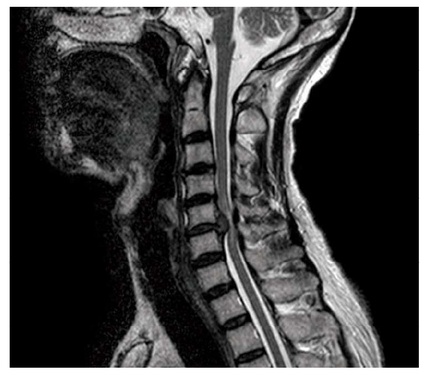

56歳の男性。数年前から頸椎椎間板ヘルニアを指摘されていた。昨日、自宅で転倒して突然に麻痺を呈した。頸髄損傷と診断され、主な損傷部位以下の機能はASIA機能障害尺度[ASIA Impairment Scale〈AIS〉]でBである。頸椎MRI を別に示す。正しいのはどれか。